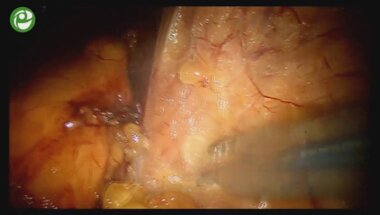

Лапароскопическая резекция левой почки с опухолевым узлом

26 дек 2015

Лапароскопическая роботизированная резекция почки

27 дек 2015

Ретроперитонеоскопическая резекция почки с опухолью

25 дек 2015